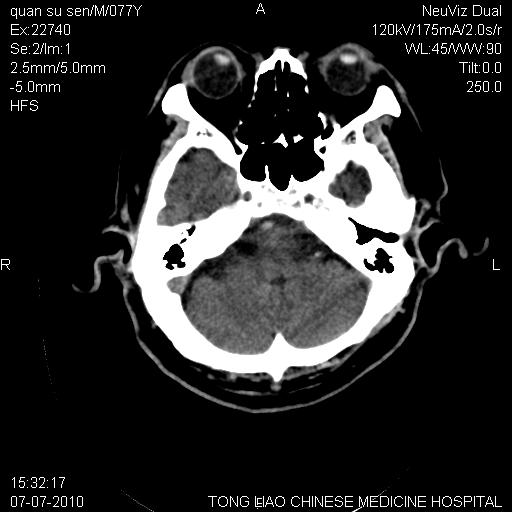

标题: CT27542:小脑病灶

平时经常遇到这样的病例,请问大家,是小脑萎缩还是小脑梗塞?

第一例,头晕、呕吐,复视,左侧肢体麻木

都是单侧小脑半球出现片状低密度灶,可以诊断脑萎缩吗?还是小脑梗塞?